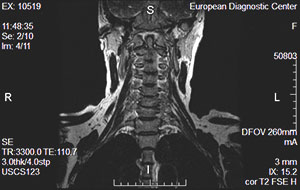

ΠΠ°Π³Π½ΠΈΡΠ½ΠΎ-ΡΠ΅Π·ΠΎΠ½Π°Π½ΡΠ½Π°Ρ ΡΠΎΠΌΠΎΠ³ΡΠ°ΡΠΈΡ ΡΠΊΠ°Π·Π°Π½Π½ΠΎΠΉ ΠΎΠ±Π»Π°ΡΡΠΈ, Π²Π°ΡΠΈΠ°Π½Ρ Π½ΠΎΡΠΌΡ

ΠΠΎΡΠΏΠ°Π»ΠΈΡΠ΅Π»ΡΠ½ΡΠ΅ Π·Π°Π±ΠΎΠ»Π΅Π²Π°Π½ΠΈΡ ΠΈ ΠΎΠ±ΡΠ΅ΠΌΠ½ΡΠ΅ ΠΎΠ±ΡΠ°Π·ΠΎΠ²Π°Π½ΠΈΡ ΡΠ΅ΠΈ ΡΠ°ΡΡΠΎ Π²ΡΡΡΠ΅ΡΠ°ΡΡΡΡ Π² Ρ ΠΈΡΡΡΠ³ΠΈΡΠ΅ΡΠΊΠΎΠΉ ΠΏΡΠ°ΠΊΡΠΈΠΊΠ΅. ΠΠΈΡΡΠ΅ΡΠ΅Π½ΡΠΈΠ°ΡΠΈΡ ΠΏΠ°ΡΠΎΠ»ΠΎΠ³ΠΈΠΉ Π²ΡΠ·ΡΠ²Π°Π΅Ρ ΡΡΡΠ΄Π½ΠΎΡΡΠΈ ΠΈΠ·-Π·Π° ΡΠ»ΠΎΠΆΠ½ΠΎΠΉ Π°Π½Π°ΡΠΎΠΌΠΈΠΈ ΡΠ°ΡΡΠΌΠ°ΡΡΠΈΠ²Π°Π΅ΠΌΠΎΠΉ ΠΎΠ±Π»Π°ΡΡΠΈ ΠΈ ΡΡ ΠΎΠΆΠ΅ΡΡΠΈ ΠΊΠ»ΠΈΠ½ΠΈΡΠ΅ΡΠΊΠΈΡ ΠΏΡΠΎΡΠ²Π»Π΅Π½ΠΈΠΉ. ΠΠ Π’ ΠΏΠΎΠ·Π²ΠΎΠ»ΡΠ΅Ρ ΠΏΠΎΠ»ΡΡΠΈΡΡ ΠΏΠΎΠ΄ΡΠΎΠ±Π½ΡΠ΅ ΠΈΠ·ΠΎΠ±ΡΠ°ΠΆΠ΅Π½ΠΈΡ ΠΌΡΠ³ΠΊΠΎΡΠΊΠ°Π½Π½ΡΡ ΠΈ ΠΊΠΎΡΡΠ½ΡΡ ΡΡΡΡΠΊΡΡΡ, ΠΎΠΏΠΈΡΠ°ΡΡΡ Π½Π° ΠΏΡΠΈΠ½ΡΠΈΠΏ ΠΌΠ°Π³Π½ΠΈΡΠ½ΠΎΠ³ΠΎ ΡΠ΅Π·ΠΎΠ½Π°Π½ΡΠ°. ΠΠΎΠΌΠΏΡΡΡΠ΅ΡΠ½Π°Ρ ΠΏΡΠΎΠ³ΡΠ°ΠΌΠΌΠ° ΠΏΡΠ΅ΠΎΠ±ΡΠ°Π·ΡΠ΅Ρ Π΄Π°Π½Π½ΡΠ΅ Π² ΡΠ΅ΡΠΈΡ ΡΡΠ΅Π·ΠΎΠ² ΠΈ ΡΠΎΡΠΌΠΈΡΡΠ΅Ρ ΠΎΠ±ΡΠ΅ΠΌΠ½ΡΡ ΠΊΠ°ΡΡΠΈΠ½ΠΊΡ, ΠΊΠΎΡΠΎΡΡΡ ΠΌΠΎΠΆΠ½ΠΎ ΡΠ²Π΅Π»ΠΈΡΠΈΠ²Π°ΡΡ ΠΈ ΡΠ°ΡΡΠΌΠ°ΡΡΠΈΠ²Π°ΡΡ Π² Π»ΡΠ±ΠΎΠΉ ΠΏΠ»ΠΎΡΠΊΠΎΡΡΠΈ. Π’ΠΎΠ»ΡΠΈΠ½Ρ ΡΡΠ΅Π·Π° ΡΡΡΠ°Π½Π°Π²Π»ΠΈΠ²Π°Π΅Ρ Π²ΡΠ°Ρ Π² Π·Π°Π²ΠΈΡΠΈΠΌΠΎΡΡΠΈ ΠΎΡ ΠΏΡΠ΅Π΄ΠΏΠΎΠ»Π°Π³Π°Π΅ΠΌΠΎΠ³ΠΎ Π΄ΠΈΠ°Π³Π½ΠΎΠ·Π°, ΡΠ΅Π»Π΅ΠΉ ΠΈ Π·Π°Π΄Π°Ρ ΠΈΡΡΠ»Π΅Π΄ΠΎΠ²Π°Π½ΠΈΡ.

ΠΠ°Π³Π½ΠΈΡΠ½ΠΎ-ΡΠ΅Π·ΠΎΠ½Π°Π½ΡΠ½Π°Ρ ΡΠΎΠΌΠΎΠ³ΡΠ°ΡΠΈΡ ΠΌΡΠ³ΠΊΠΈΡ ΡΠΊΠ°Π½Π΅ΠΉ ΡΠ΅ΠΈ ΠΏΠΎΠ·Π²ΠΎΠ»ΡΠ΅Ρ ΠΈΡΡΠ»Π΅Π΄ΠΎΠ²Π°ΡΡ ΡΠΎΡΡΠΎΡΠ½ΠΈΠ΅ ΠΌΡΡΡ ΠΈ ΡΡΡ ΠΎΠΆΠΈΠ»ΠΈΠΉ, Π»ΠΈΠΌΡΠΎΡΠ·Π»ΠΎΠ², ΡΠΎΡΡΠ΄ΠΎΠ² ΠΈ ΠΎΡΡΠ°Π»ΡΠ½ΡΡ ΡΡΡΡΠΊΡΡΡ, ΡΠ°ΡΠΏΠΎΠ»ΠΎΠΆΠ΅Π½Π½ΡΡ Π² Π΄Π°Π½Π½ΠΎΠΉ ΠΎΠ±Π»Π°ΡΡΠΈ. ΠΠ Π’ ΡΡΠΈΡΠ°Π΅ΡΡΡ ΠΎΠ΄Π½ΠΈΠΌ ΠΈΠ· ΡΠ°ΠΌΡΡ Π±Π΅Π·ΠΎΠΏΠ°ΡΠ½ΡΡ ΠΈ ΠΈΠ½ΡΠΎΡΠΌΠ°ΡΠΈΠ²Π½ΡΡ Π΄ΠΈΠ°Π³Π½ΠΎΡΡΠΈΡΠ΅ΡΠΊΠΈΡ ΠΏΡΠΎΡΠ΅Π΄ΡΡ. ΠΠ»Π°Π³ΠΎΠ΄Π°ΡΡ Π΄Π°Π½Π½ΠΎΠΌΡ Π²ΠΈΠ΄Ρ Π΄ΠΈΠ°Π³Π½ΠΎΡΡΠΈΠΊΠΈ ΠΌΠΎΠΆΠ½ΠΎ Π²ΡΡΠ²ΠΈΡΡ ΠΈΡΡΠΈΠ½Π½ΡΡ ΠΏΡΠΈΡΠΈΠ½Ρ ΡΡΠ΅Π²ΠΎΠΆΠ°ΡΠΈΡ ΡΠΈΠΌΠΏΡΠΎΠΌΠΎΠ² ΠΈ ΡΠΎΡΠ½ΠΎ ΠΎΠΏΡΠ΅Π΄Π΅Π»ΠΈΡΡ Π΄ΠΈΠ°Π³Π½ΠΎΠ·, Π½Π° ΠΎΡΠ½ΠΎΠ²Π΅ ΠΊΠΎΡΠΎΡΠΎΠ³ΠΎ Π±ΡΠ΄Π΅Ρ Π½Π°Π·Π½Π°ΡΠ΅Π½ΠΎ Π»Π΅ΡΠ΅Π½ΠΈΠ΅. ΠΡΠΎΠΌΠ΅ ΡΠΎΠ³ΠΎ, ΠΏΡΠΎΡΠ΅ΡΡ ΠΏΠΎΠ»ΡΡΠ΅Π½ΠΈΡ ΡΠ½ΠΈΠΌΠΊΠΎΠ² Π±Π΅Π·Π±ΠΎΠ»Π΅Π·Π½Π΅Π½ ΠΈ Π½Π΅ Π²ΡΠ·ΡΠ²Π°Π΅Ρ Ρ ΠΏΠ°ΡΠΈΠ΅Π½ΡΠ° Π½ΠΈΠΊΠ°ΠΊΠΎΠ³ΠΎ Π΄ΠΈΡΠΊΠΎΠΌΡΠΎΡΡΠ°.